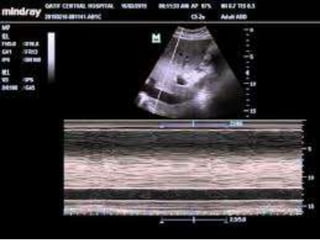

Technique

• We use low frequency probe or abdominal

probe.

• The transducer position is just below the

xiphisternum 1-2 cms to the right of midline

with the marker dot pointing towards the

sternum notch.

• M-mode line is placed through the IVC

2-3cms from the junction between IVC and

right atrium or 0.5-1 cm from the junction

of hepatic vien.

Technique • We uselow frequency probe or abdominal probe. • The transducer position is just below the xiphisternum 1-2 cms to the right of midline with the marker dot pointing towards the sternum notch.

• M-mode lineis placed through the IVC 2-3cms from the junction between IVC and right atrium or 0.5-1 cm from the junction of hepatic vien.